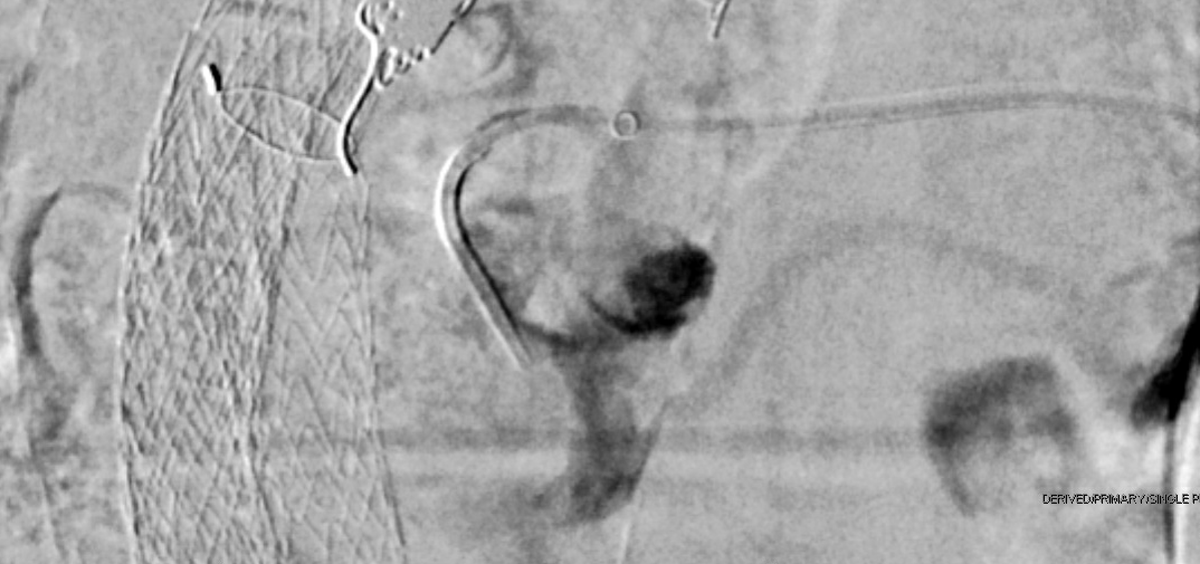

The day continued with a post renal biopsy bleed with active extravasation and a pseudoaneurysm, both of which were easily addressed with LAVA-18. Both patients are doing well after successful procedures. @SirtexMedical @thegestgroup